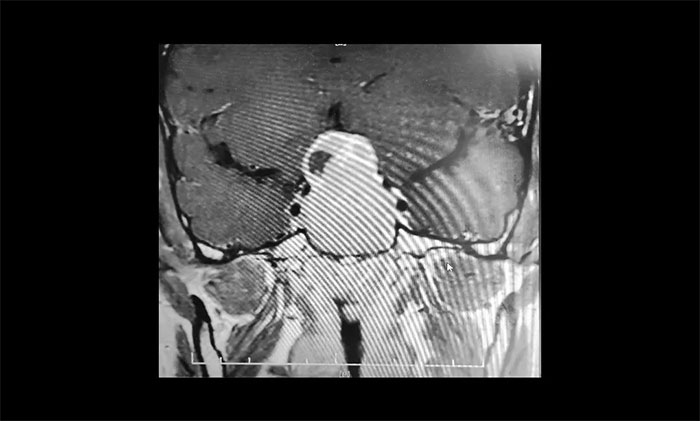

▲ 術(shù)前影像:巨大垂體瘤,向鞍上生長

為了進一步確定瘤體的位置和大小,當即進行了鞍區(qū)MRI平掃+增強。影像顯示,蝶鞍顯著擴大,鞍區(qū)見一“塔樣”腫塊灶,病變總矢橫高徑約3.5×4.5×5cm。瘤體向鞍上生長,占據(jù)鞍上池,明顯推移視交叉、分界模糊,三腦室前下部受壓變形。鞍底塌陷、蝶竇填充;侵及包繞兩側(cè)海綿竇約1/2,海綿竇向外側(cè)移位。

結(jié)合影像檢查,潘仁龍主任、李士其教授會診后一致達成共識。由于巨大垂體瘤長期壓迫視神經(jīng),患者視物出現(xiàn)異常,右眼已經(jīng)失明,手術(shù)指征明顯,應盡快手術(shù),盡可能挽救患者視力。